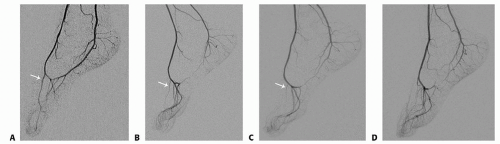

Routine angiography is debatable; nevertheless, it is the authors’ practice to obtain angiography of the hand and foot on most patients (FIG 4).

Angiography helps to create a road map and a plan for the operation. Questions such as the need for vein grafting (foot), end-to-side vs end-to-end anastomoses (hand), and residual vascularity of the foot after flap harvest can be answered preoperatively. This planning is essential in cases where a team approach with multiple surgeons is undertaken. Certainly for patients with abnormal foot anatomy (FIG 5), angiography helps with preoperative planning to ensure a viable flap.

FIG 4 • Angiographic variation in arterial anatomy of the foot (FDMA indicated by white arrow). The variations outlined in FIG 1 are seen in the angiograms, with a large, dominant FDMA (A); a thinner, intramuscular FDMA (B); a diminutive FDMA (C); and no FDMA (D). The plantar system is dominant in B to D.